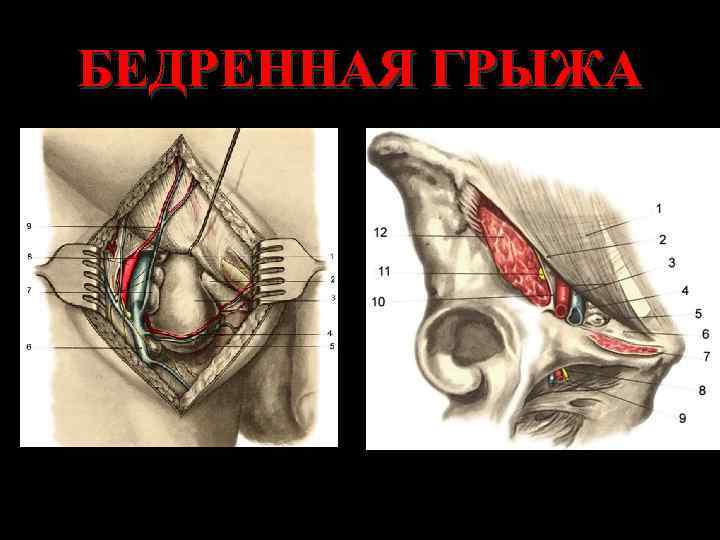

БЕДРЕННАЯ ГРЫЖА

СПОСОБЫ ПЛАСТИКИ ПРИ БЕДРЕННОЙ ГРЫЖЕ • Пластика по Бассини • Пластика по Руджи-Парлавеччи • Ненатяжная пластика